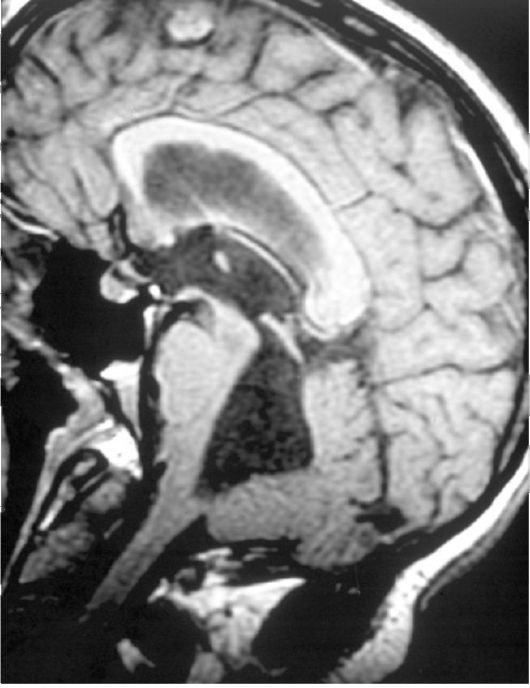

МРТ снимки мальформации Денди-Уокера